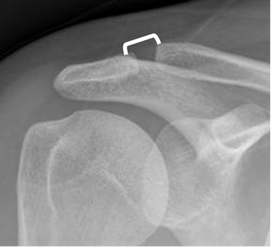

Fig 53. Articulación acromioclavicular.

Rx AP. Aumento del espacio en la articulación acromioclavicular. Puede corresponder a un hallazgo normal o patológico.